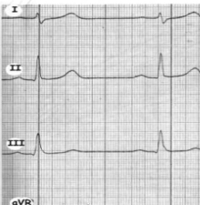

Ermittlung der höchsten Zacke:

Abl. III => Rechtstyp

Abl. II ist positiv

Abl. I überwiegend negativ